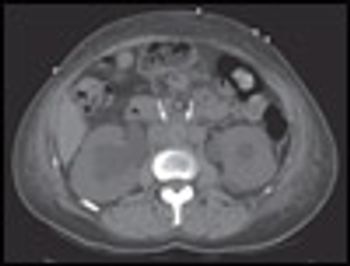

A 53-year-old woman presented with sudden onset of left upper quadrant abdominal pain. She had a history of atrial fibrillation, hypertension, and congestive heart failure.